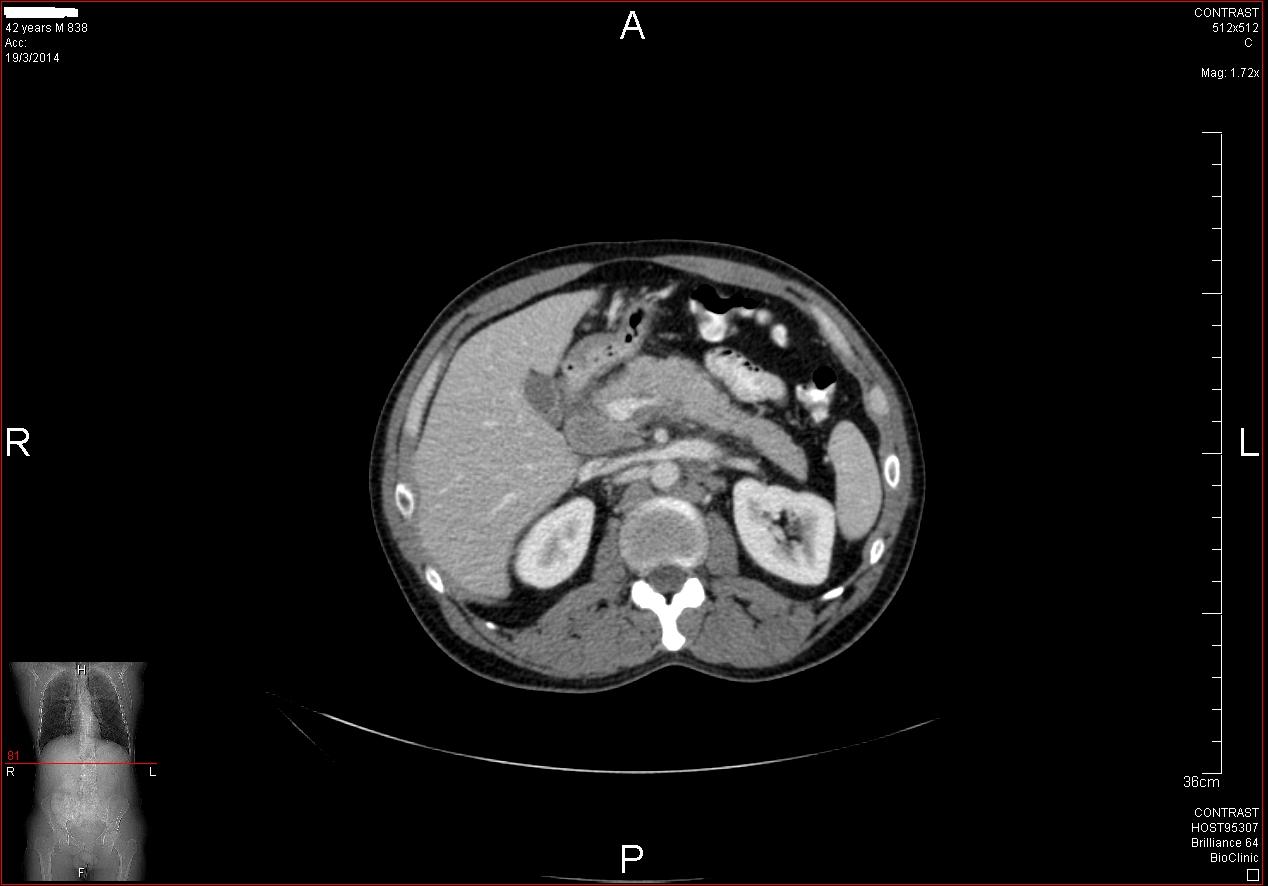

2) Αδενοκαρκίνωμα παγκρέατος

Άνδρας 68 ετών, χωρίς προηγούμενο ατομικό ή οικογενειακό ιστορικό, διαγνώσθηκε με σακχαρώδη διαβήτη από τον παθολόγο του σε εργαστηριακό έλεγχο ρουτίνας.

Στα πλαίσια διερεύνησης του πρωτοεμφανιζόμενου διαβήτη, υποβλήθηκε σε μαγνητική τομογραφία άνω κοιλίας (MRI/MRCP) που ανέδειξε μια συμπαγή μάζα στην κεφαλή του παγκρέατος, διαμέτρου περίπου 2εκ και μεγάλη διάταση του παγκρεατικού πόρου.

Ο ασθενής υποβλήθηκε σε ενδοσκοπικό υπέρηχο που έδειξε μια υποηχοϊκή μάζα διαμέτρου 21 χιλιοστών, με σαφή όρια, στην παγκρεατική κεφαλή και μεγάλη διάταση του χοληδόχου πόρου και του παγκρεατικού πόρου (διάμετρος 12 χιλιοστά).

Η μάζα είχε ξεκάθαρο διαχωριστικό όριο λίπους από την άνω μεσεντέριο φλέβα και δεν διηθούσε κανένα άλλο μεγάλο αγγείο της περιοχής (πυλαία φλέβα, σπληνοπυλαία συμβολή και αρτηρίες). Έγινε βιοψία με λεπτή βελόνη (FNA Χ3) και το κυτταρολογικό υλικό ήταν θετικό για αδενοκαρκίνωμα παγκρέατος. Το νεόπλασμα κρίθηκε χειρουργήσιμο και ο ασθενής υποβλήθηκε σε επέμβαση Whipple κατά την οποία αφαιρέθηκε πλήρως η παγκρεατική κεφαλή και ο όγκος σε υγιή όρια αλλά και 12 λεμφαδένες που ήταν όλοι αρνητικοί για κακοήθεια. Ο ασθενής υποβάλλεται σε συμπληρωματική χημειοθεραπεία.